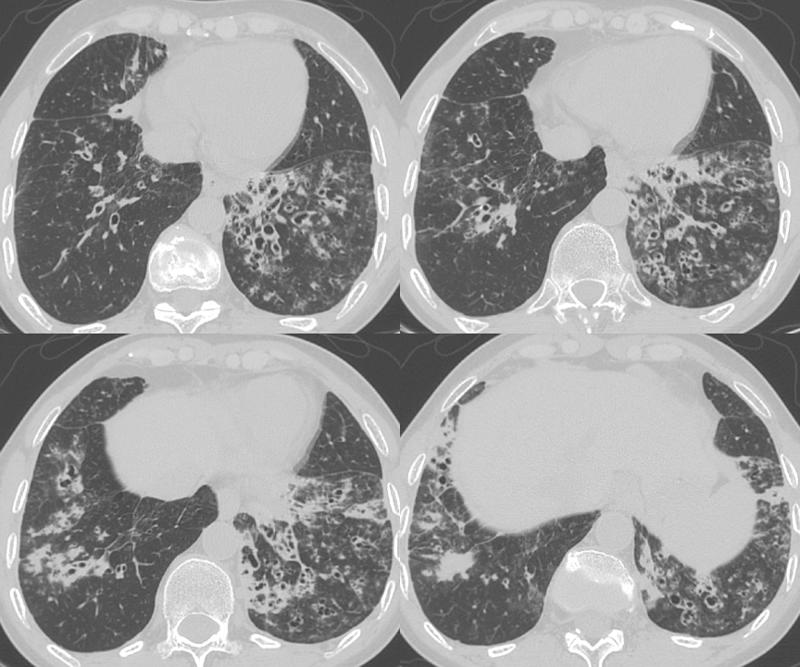

Bronchiectasis

Bronchiectasis Case 14